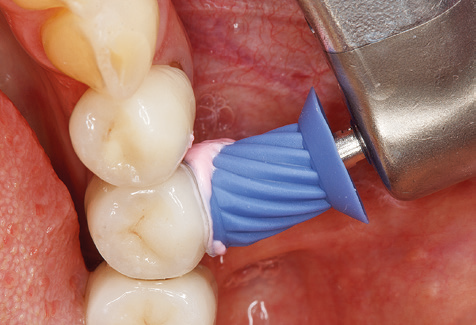

Naturalmente, anche i consigli di lavoro per la pulizia delle superfici degli impianti sono indispensabili per SPT nei pazienti dotati di impianti. L'inserto per la pulizia dell'impianto in questo casoi è caratterizzato dal suo design affusolato ed esagonale. Questo design consente una penetrazione leggera e atraumatica nella tasca perimplantare e mostra buone prestazioni di pulizia (Fig. 7).